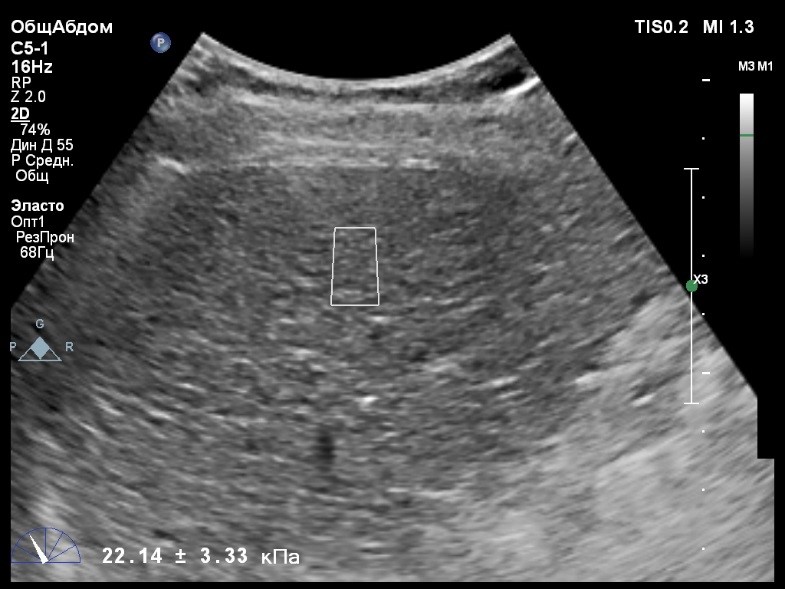

Пациент обратился к доктору с направлением на исследование степени жесткости печени в июне 2017 года. Из истории болезни, пациент страдает Гепатитом С с 2014 года. Лечение не получал. Транзиентная эластография показала не коррективные значения степени жесткости печени по причине сопутствующего поликистоза печени. На момент настоящего исследования, пациент не принимал пищу на протяжении 4 часов, АСТ, АЛТ не превышают патологических значений. Для оценки жесткости была выбрана технология компании Philips ElastPQ (точечная эластография) и прибор компании Philips Epiq 7 Исследование было проведено в соответствии с клиническими рекомендациями для ультразвуковых приборов компании Philips. В результате исследования были получены следующие результаты:

| 1 [7.95] kPa | 2 [8.73] kPa | 3 [8.11] kPa |

| 4 [9.32] kPa | 5 [8.05] kPa | 6 [9.52] kPa |

| 7 [8.66] kPa | 8 [7.36] kPa | 9 [8.54] kPa |

| 10 [8.30] kPa | 11 [6.56] kPa | 12 [7.14] kPa |

| 13 [7.47] kPa | 14 [6.56] kPa | 15 [6.56] kPa |

Стандартное Отклонение [0.85] kPa Медиана Жесткости [8.05] kPa Фактор Качества IQR/Med 10%

Зона интереса расположена на более чем на один сантиметр глубже капсулы, параллельно ходу луча, в середине изображения, в участке печени лишенном кист.

Капсула видна как белая линия перпендикулярная ходу ультразвукового луча, исследования производятся приблизительно в одном и том же сегменте печени.

Стандартное отклонение (2,26 kPA) не превышает 30 процентов от полученного значения (8,54 kPA).

Для интерпретации полученных клинических данных были использованы Рекомендации по проведению эластографии сдвиговой волной для оценки жесткости печени при использовании ультразвуковых аппаратов компании Филипс с примером протокола. Техническая сложность проведения слепой эластометрии печени связана с сопутствующим поликистозом органа и диагностическим методом выбора в данной ситуации является Эластография с возможностью визуального контроля положения контрольного объема. Подготовка пациента соответствовала проводимому исследованию. Представленные слайды проведенного исследования свидетельствуют о правильном техническом исполнении проб, отсутствием в поле контрольного объема кистозных образований, что позволяет заключиться о достоверности полученных измерений. Таким образом, учитывая полученную медиану жесткости на уровне 8,05 кРа (6.56 – 9.52 kPa) и уровень стандартных отклонений не превышающих 30%, полагаю, что уровень степени фиброза соответствует стадии F2. Заведующий отделением УЗД МЦ «Асклепий», Глушенко Д. Е.